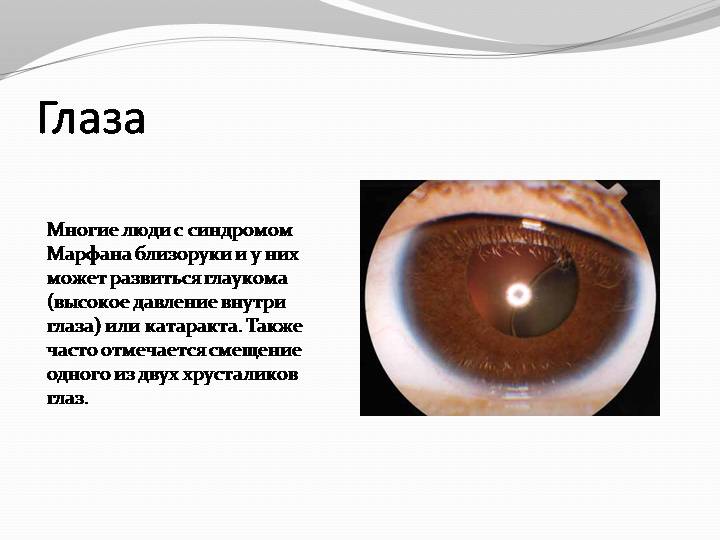

Neonatalnaya forma sindroma marfana klinicheskoe opisanie i kompleksnyj podhod k diagnostike i lecheniyu tema nauchnoj stati po klinicheskoj medicine chitajte besplatno tekst nauchno issledovatelskoj raboty v elektronnoj biblioteke kiberleninka (Тип файлу jpg)

Neonatalnaya Forma Sindroma Marfana Klinicheskoe Opisanie I Kompleksnyj Podhod K Diagnostike I Lecheniyu Tema Nauchnoj Stati Po Klinicheskoj Medicine Chitajte Besplatno Tekst Nauchno Issledovatelskoj Raboty V Elektronnoj Biblioteke Kiberleninka

Neonatalnaya forma sindroma marfana klinicheskoe opisanie i kompleksnyj podhod k diagnostike i lecheniyu tema nauchnoj stati po klinicheskoj medicine chitajte besplatno tekst nauchno issledovatelskoj raboty v elektronnoj biblioteke kiberleninka (Тип файлу jpg)

Neonatalnaya Forma Sindroma Marfana Klinicheskoe Opisanie I Kompleksnyj Podhod K Diagnostike I Lecheniyu Tema Nauchnoj Stati Po Klinicheskoj Medicine Chitajte Besplatno Tekst Nauchno Issledovatelskoj Raboty V Elektronnoj Biblioteke Kiberleninka